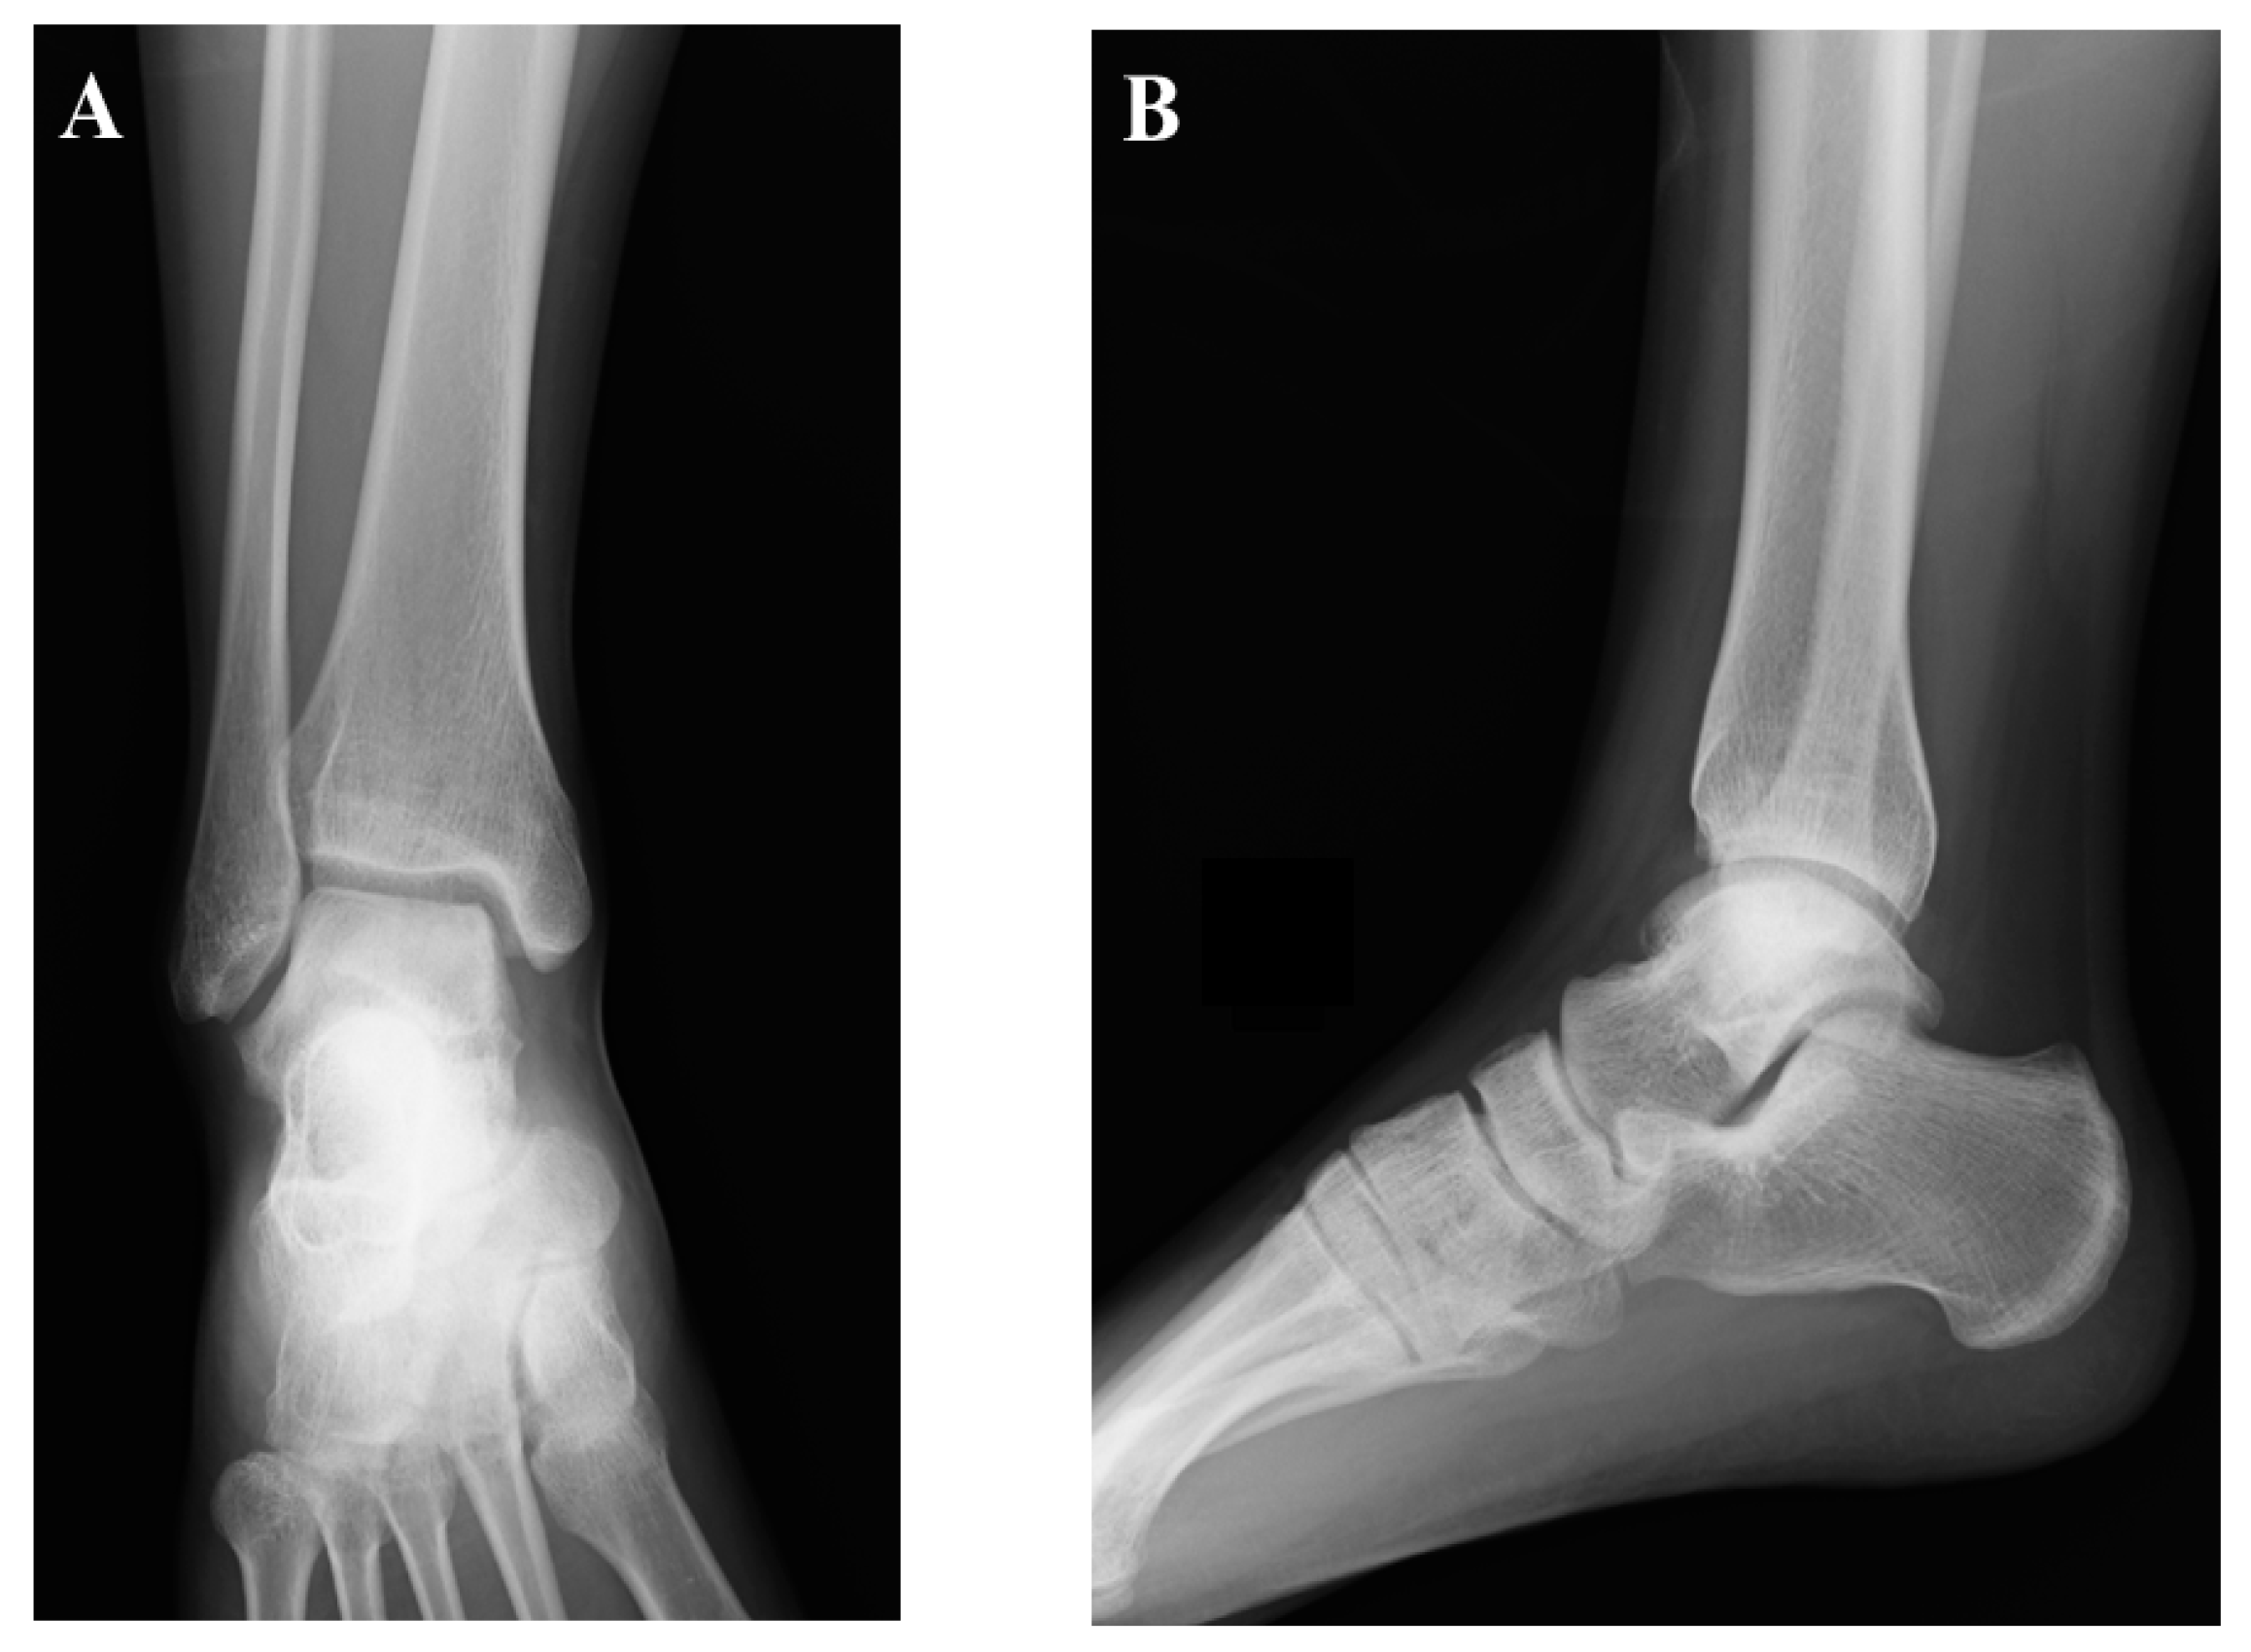

2.1. Preoperative Evaluation